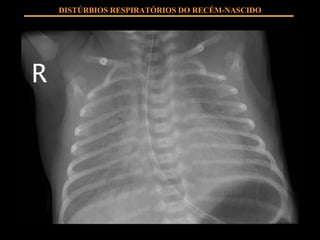

QUADRO CLÍNICO Estigmas de prematuridade Taquipnéia Esforço respiratório Cianose Hipoventilação DISTÚRBIOS RESPIRATÓRIOS DO RECÉM-NASCIDO